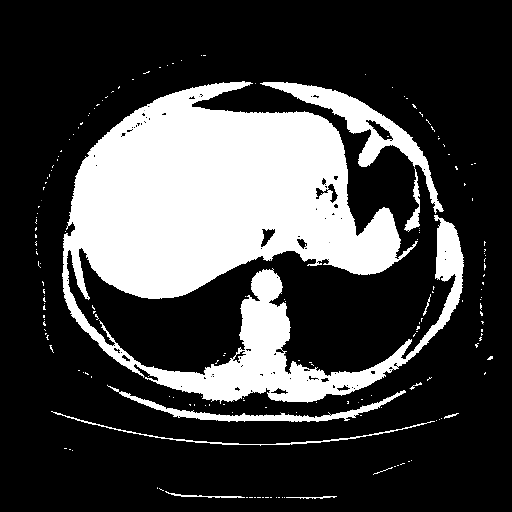

Reconstructed NATIVE CT scan (cycle consistency)

Full window (WL 1023.5, WW 4095 β†’ Low βˆ’1024, High +3071)

Actual HU range: [-1024.0, 3071.0]